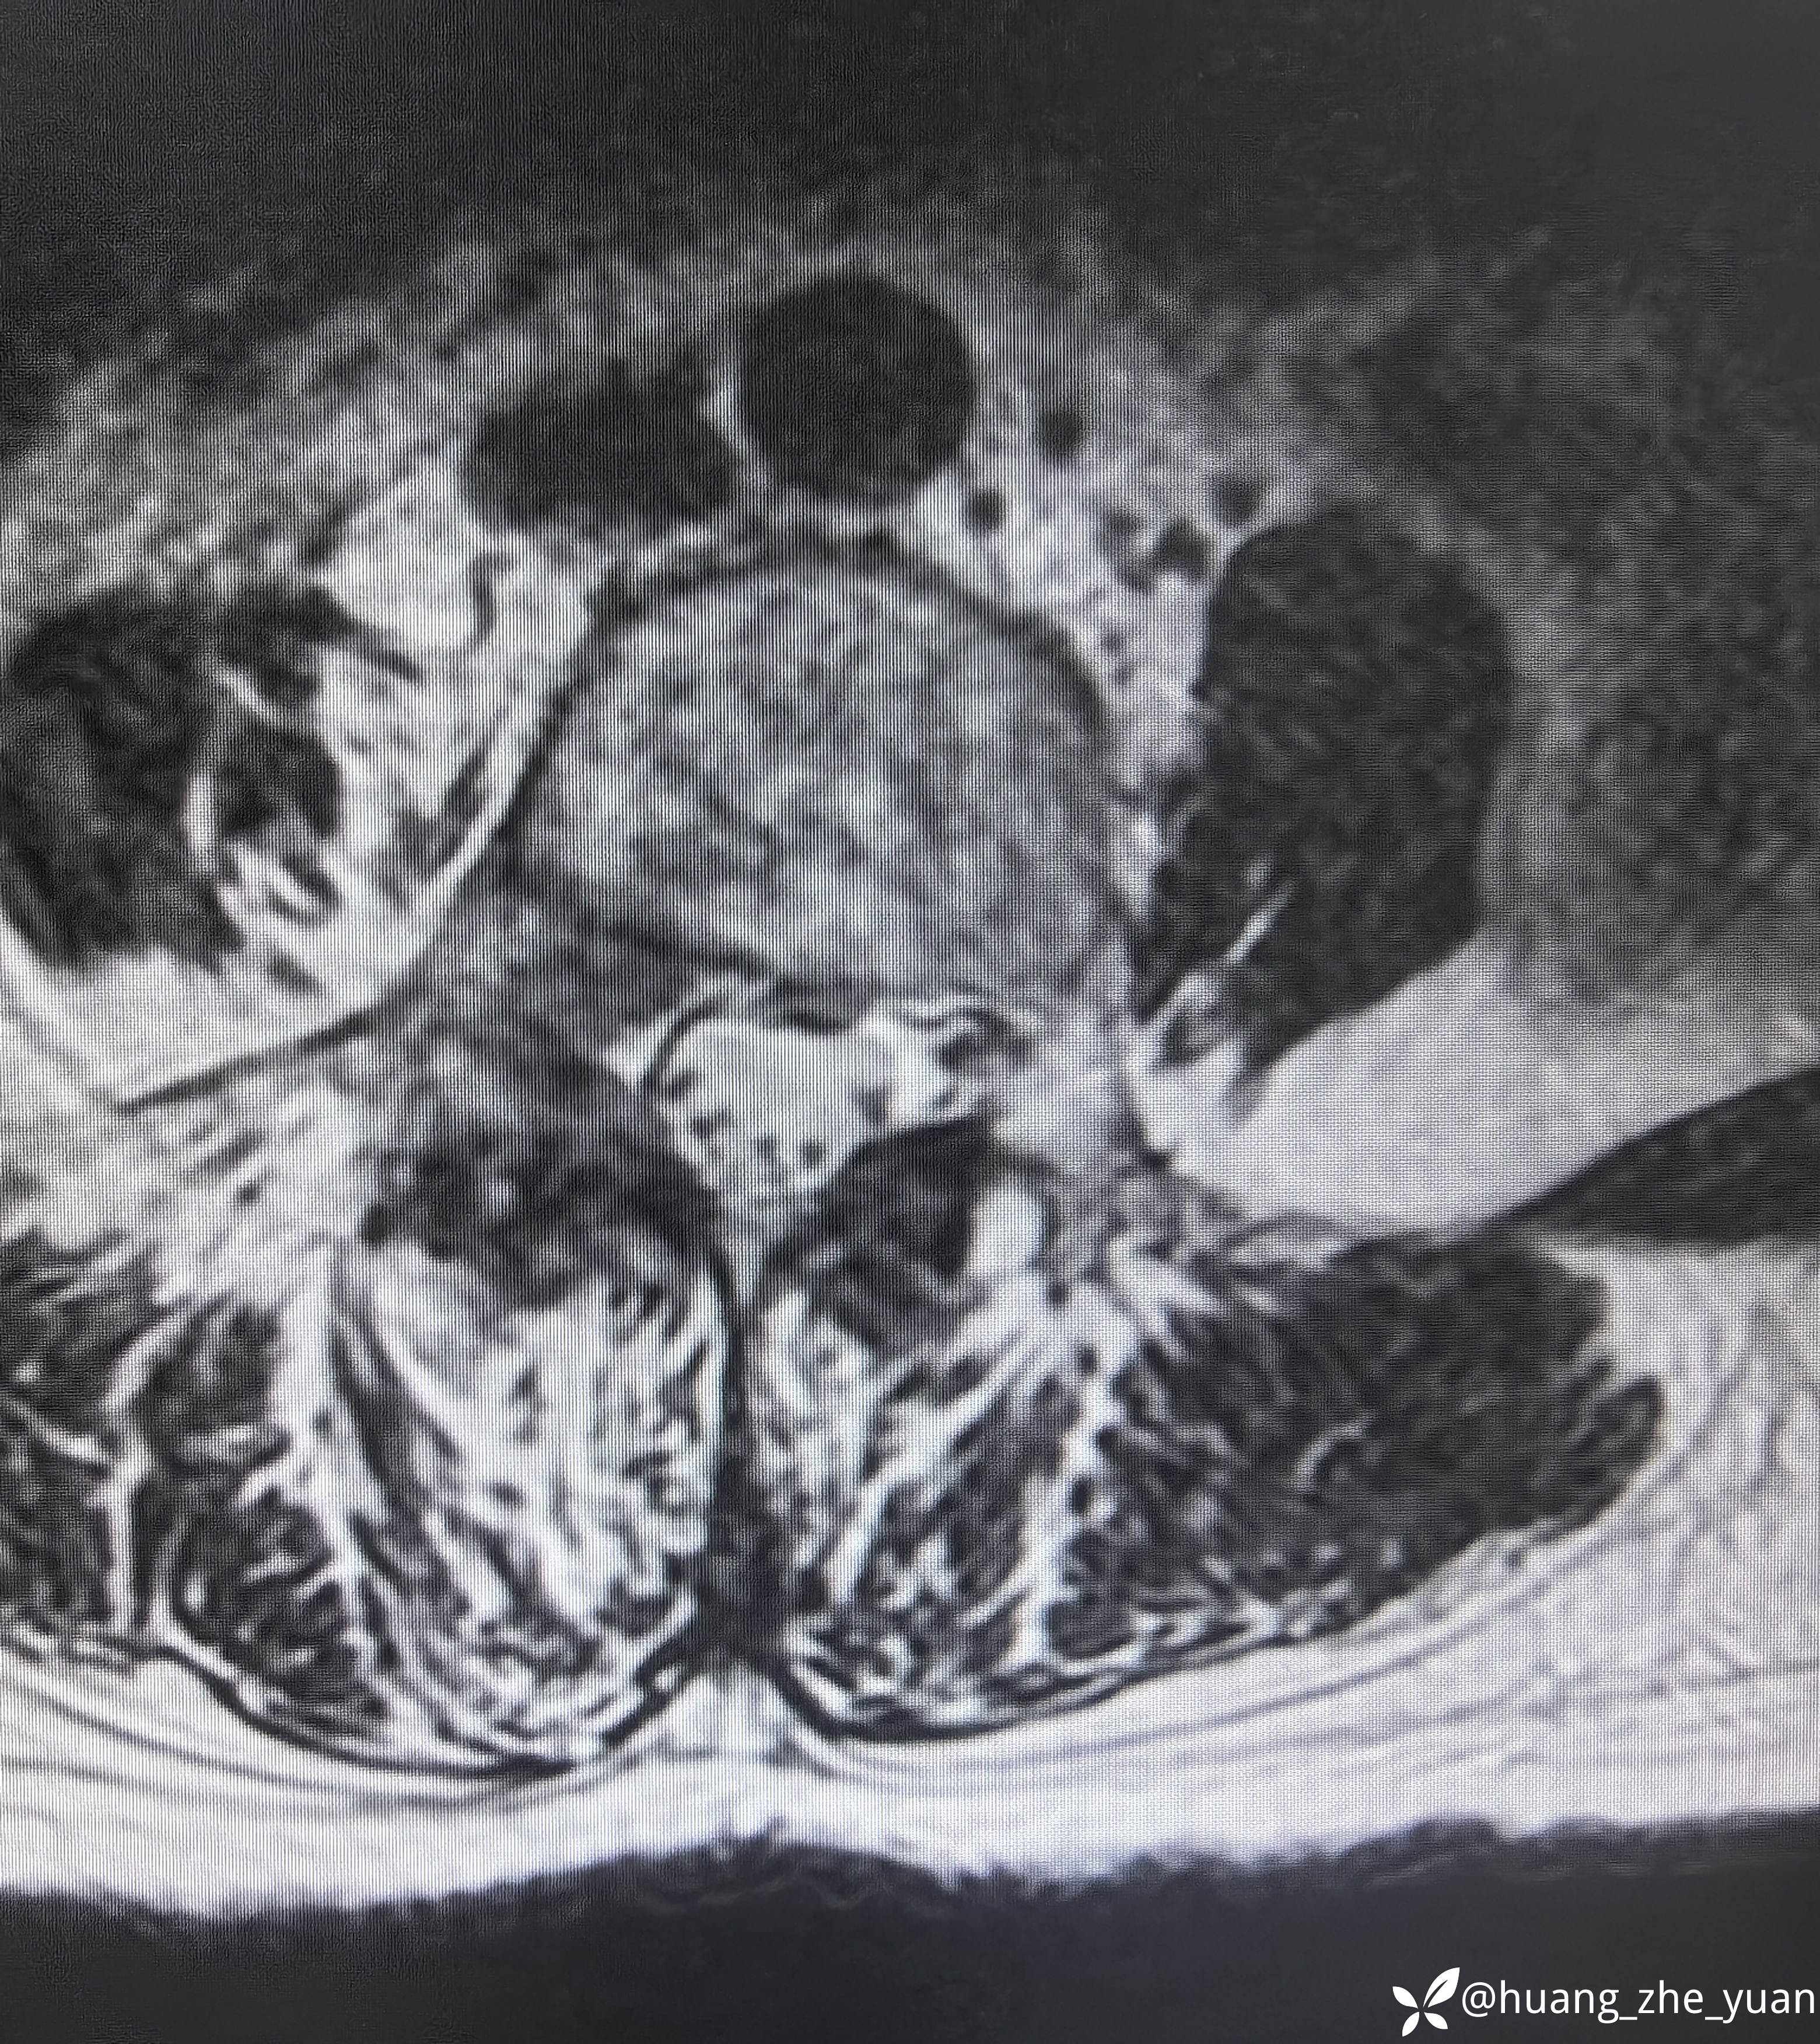

70岁女性,反复右下肢放射痛八个月。合并症:糖尿病,胰岛素泵控制。